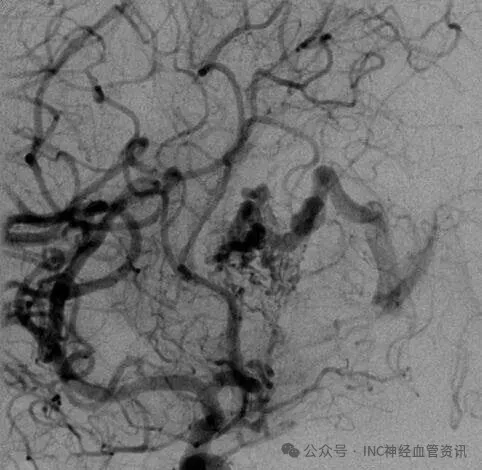

Anna的AVM由多条动脉供血:ACA/PcaA分支、ACoA穿支和mPChA,形成了一个复杂的血管网络。首次伽马刀治疗后,血管团部分闭塞,但残留的畸形血管仍然构成出血威胁。

▼该AVM由ACA/PcaA分支、ACoA穿支和mPChA供血[右侧ICA造影